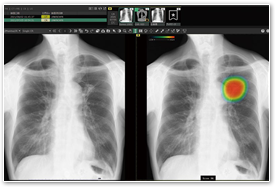

胸部X線画像病変検出ソフトウェア

(CXR-AID富士フィルム)

そがわ医院|デジタル撮影した胸部単純X線画像を自動AI解析。

結節・腫瘤影、浸潤影、気胸が疑われる肺領域を検出しマーキングします。

そがわ医院|その肺領域を医師が再確認することで、見落し防止を支援します。